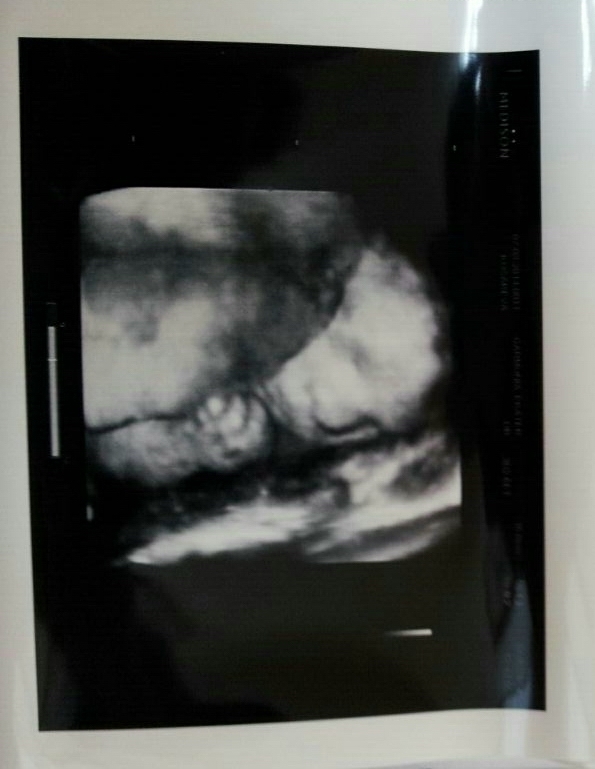

Наше 4 д узи на 30 неделе.

УЗИ, КТГ, доплерСходили мы на 4 д в 30 недель, эмоций море, как же это прекрасно!!!Всем огромное спасибо за советы, мы остались очень довольны результатом, Всем советую!!!Наше маленькое солнышко вел себя хорошо, порадовал папулю и мамулю.С самого начала он прикрывал свои сладкие губочки ручками, маме пришлось слегка покрутиться и мы были у цели.Какой же ты славный сыночек наш, пухленькие губки и щечки, носик картошечкой, так и хочется тебя расцеловать,мы тебя очень любим и ждем!!!Самое клевое это когда тетя угостила маму конфеточкой и сказала, сейчас начнется смотрите.Спустя пару минут рассасывания карамельки мы обомлели от восторга, наш сладкий карапузик начал причмокивать и заглатывать воды)))ми ми ми!!!Лежим мы как положено головкой вниз,умничка наш перевернулся , а потом решили глянуть наше достоинство, краник от нас сегодня скрыли, но зато какие у нас абрикосыыыыыы, (огромные))))100 % мужичек!!!В итоге результатом узи мы очень довольны, нам дали 9 фото и диск с записью 20 минут видео